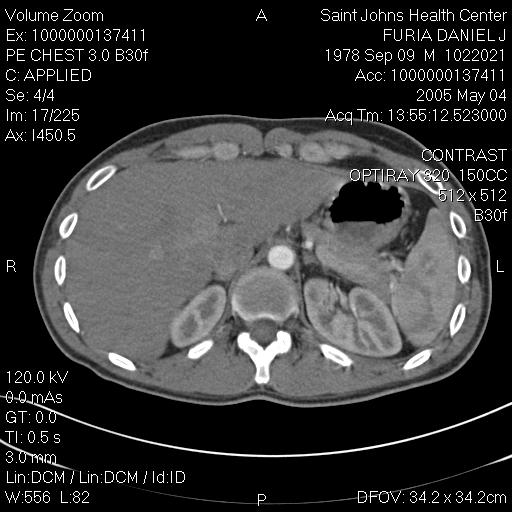

"Blebs" are weak spots that form at the top of the lung. These weak spots can leak air and cause a lung to collapse. This image shows dozens of small blebs on each of my lungs. This cat scan image was taken from above, looking down on to the top of the lung. (In other words try to imagine that you are floating up above me, looking down at the top of my head. If you could see layer by layer into my body, like the CT scan, you would then eventually see the tops of my lungs). The big dark black circle in the middle of the image is my windpipe.